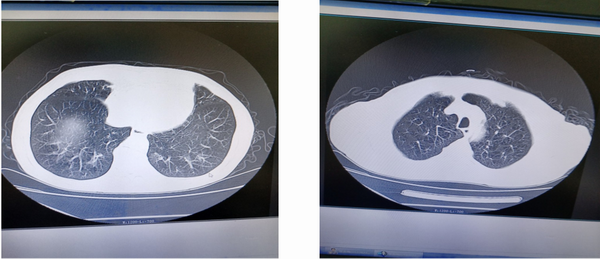

入院时症见:咳嗽,呈阵发性,晨起时明显,咯白色粘痰,量多不易咯,伴痰中带血,色暗红,具体量叙述不清,每日出现1~3次,伴喘促,以急走及爬楼后明显,休息后可缓解,时感全身乏力。入院后患者仍反复出现痰中带血的情况,入院胸部CT提示:双肺纹理增多、紊乱,肺叶透亮度增高;右肺中叶见少许纤维条索影,余肺内未见明显渗出及实质性病变;纵隔内未见肿大淋巴结;双侧胸腔未见积液。心外形不大,大血管壁钙化。右侧第8前肋陈旧性骨折。根据患者CT提示以及患者自身情况,在上海中医药大学附属岳阳中西医结合医院张恩丝老师的指导下,为进一步明确诊断以及查找咯血的原因,为爷爷完善了支气管镜检查。

爷爷气管镜检查病理结果回报:(气管镜活检物)倾向为“非小细胞性肺癌”,因组织过小,建议行免疫组化明确诊断,并排除“神经内分泌肿瘤”可能。病理的回报结果明确了诊断,也找出了反复痰中带血的原因,为后续治疗提供了更有效的依据及方向。在张老师的指导下为老爷爷进行了系统治疗,老爷爷病情平稳后已经出院,出院时已无痰中带血,同时喘促、胸闷、全身乏力等症状较前明显好转。出院后,科室人员进行了电话随访,患者诉目前没有特殊不适。

能帮助这位爷爷快速的找出反复痰中带血的原因,离不开张恩丝老师的指导以及气管镜检查技术在我院的开展。

支气管镜检查的重要意义

支气管镜检查是呼吸科医师诊断和治疗疾病不可缺少的重要手段。具有重大的临床意义:

一、气管镜检查它具有独有的优势,它能直观、清晰、清楚的看到病变,可以通过气管镜的器械通道送入活检钳,取得小米粒大小的组织送病理切片化验或者其它特殊染色对粘膜病变的性质,进行组织学定性也可以刷检或者是灌洗找脱落的细胞,如炎症的程度,癌的分化程度等进一步分级,有利于了解病变的轻重,指导制订正确的治疗方案和判断治疗的效果。

二、除了具有诊断意义外,同时还具有治疗意义,在已明确诊断的情况下,对气管、支气管腔内病变及部分腔外病变进行治疗时,如针对诊断为支气管异物的情况,可以使用异物钳等工具尽早将异物取出,避免异物堵塞气道,引起其它感染,如肺炎等。

总之,气管镜随着技术越来越成熟,在呼吸科等疾病方面的运用以及普及越来越广,为呼吸系统方面的疾病的治疗提供了福音!